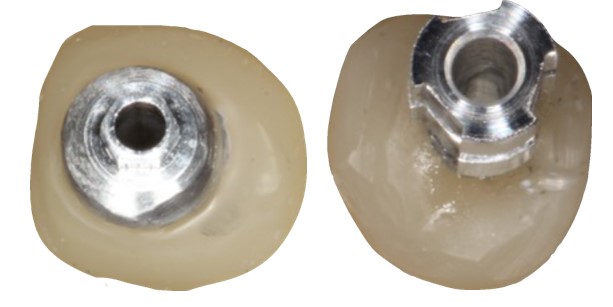

Pasul 6 – Procesul de instalare a pilonului de vindecare personalizat

Instalează bontul personalizat de vindecare în implant, utilizând șurubul de reținere disponibil împreună cu bontul temporar utilizat.

Instalează bontul personalizat de vindecare în implant, utilizând șurubul de reținere disponibil împreună cu bontul temporar utilizat.

Evaluează potrivirea clinică și radiografică adecvată cu implantul.

Umple orificiul de acces cu șurub cu un prim strat de bandă de teflon sterilă sau alt material adecvat.

Umple spațiul liber rămas al orificiului de acces cu șurub cu material compozit și fotopolimerizare.

Evacuează distanța ocluzală adecvată a bontului personalizat de vindecare și, dacă este necesar, reduce înălțimea acestuia.

Acest proces poate fi efectuat în momentul plasării implantului (protocolul cu o etapă) sau în stadiul descoperirii implantului.

Pasul 3 – Modelul de lucru Procesul de fabricație

Tehnicianul de laborator continuă cu fabricarea modelului de lucru conform practicilor normale.

Apariția gingivală personalizată generată și profilul cervical au fost înregistrate cu precizie și oferă fundamentul pentru des ignarea și fabricarea unei proteze estetice plăcute și biologice.

Tehnicianul de laborator ar trebui să utilizeze apariția generată și profilul cervical ca ghid pentru proiectarea zonei scufundate a protezei.

Se recomandă ca zona scufundată a protezei să fie fabricată din materiale biocompatibile (dioxid de titan și / sau zirconiu), astfel încât să poată asigura fundamentul pentru un rezultat stabil pe termen lung.